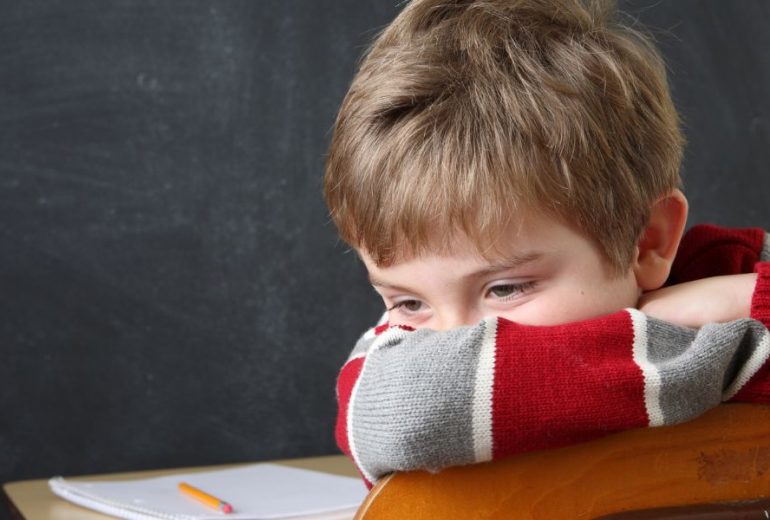

EL TDAH: un poco de luz en una visión normalmente errónea.

En reiteradas ocasiones me he encontrado a lo largo de mi carrera como profesional de la psicología con niños, adolescentes y adultos con una autoestima muy dañada por las continuas críticas recibidas a lo largo de muchos años por parte de diferentes …